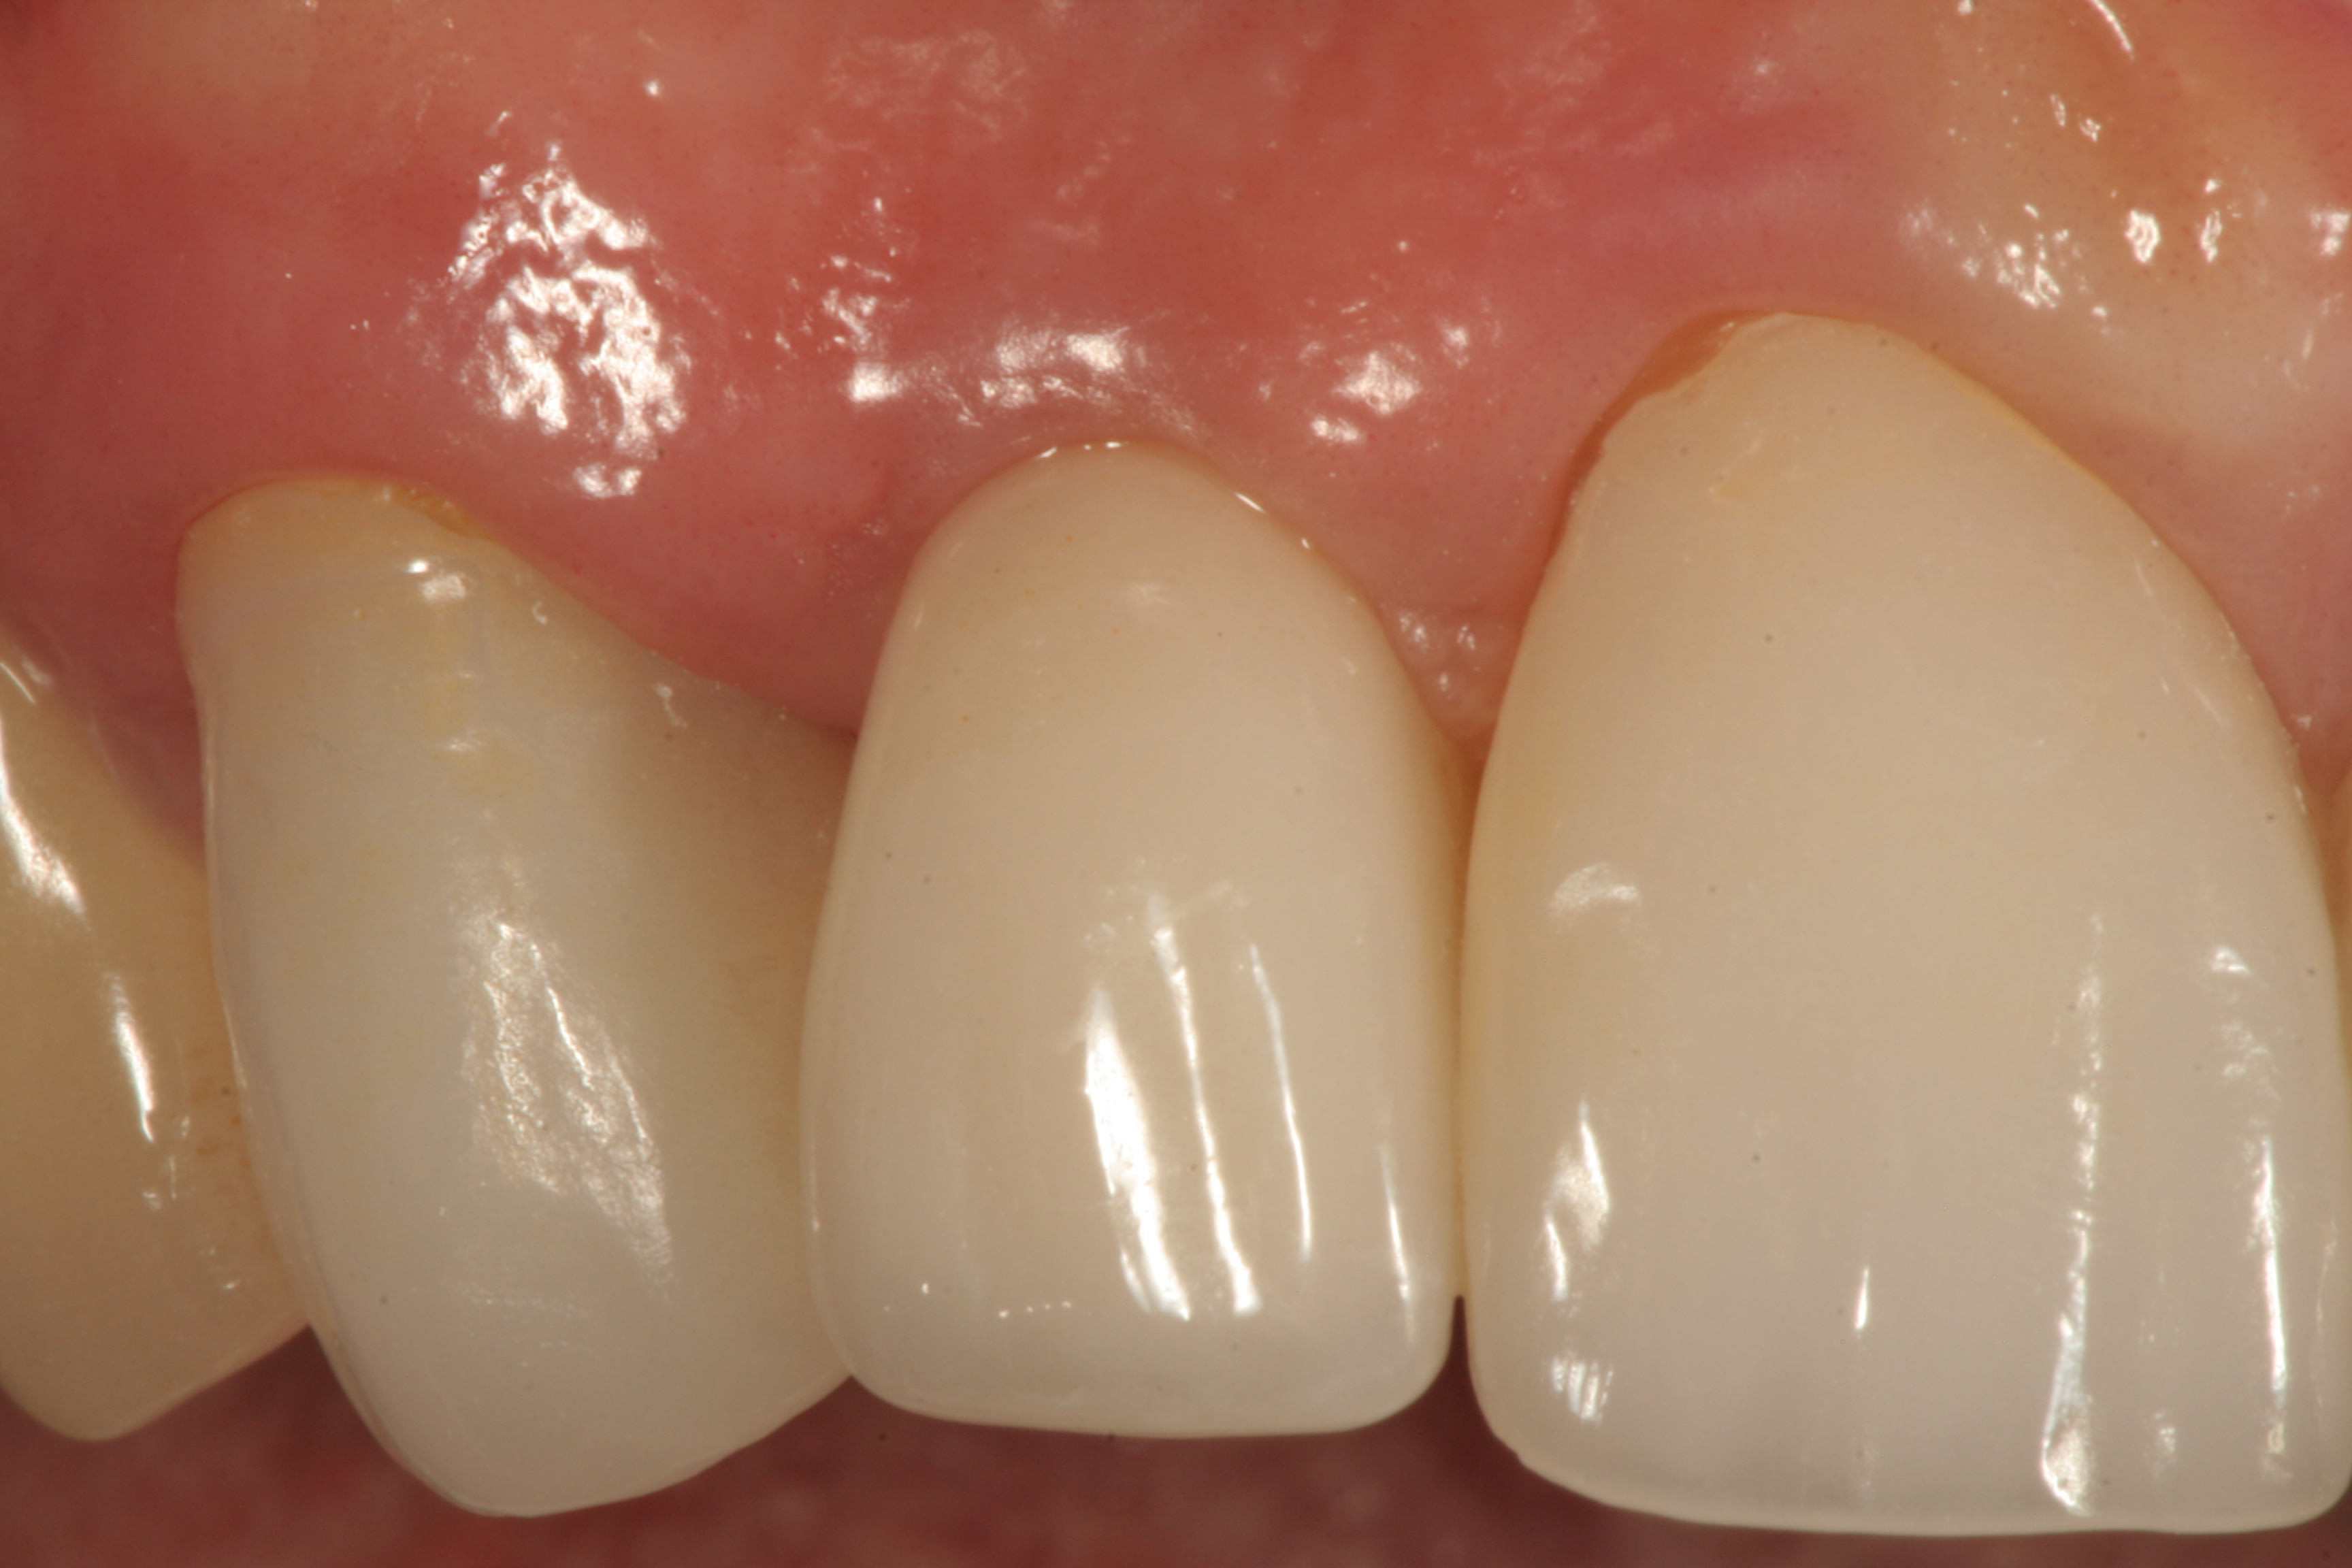

A secondary permanent Esthetic Contour Ti Abutment was modified to receive the all-ceramic restoration (IPS e.max® Ceram, Ivoclar Vivadent, www.ivoclarvivadent.com) layered upon a Procera zirconia coping (NobelProcera, Nobel Biocare, www.nobelbiocare.com). The abutment was 3.3 mm in diameter at the implant–abutment interface, resulting in a 0.5-mm platform switch.

Figure 15 shows the periapical radiograph at final crown placement (Visit 4). The abutment was screwed in place to a torque of 35 Ncm and the cement-retained crown was placed with RelyX™ Unicem (3MESPE, www.3MESPE.com); at this time only mild gingival inflammation was observed (Figure 16). One year later (18-month follow-up), an excellent esthetic result was observed from the facial aspect, with good tissue tone and no gingival recession (Figure 17).

Three years postoperatively, radiographic interpretation suggested maintenance of the crestal bone level and a stable thickness of the labial plate, from the time of implant placement throughout the follow-up period (Figure 18).